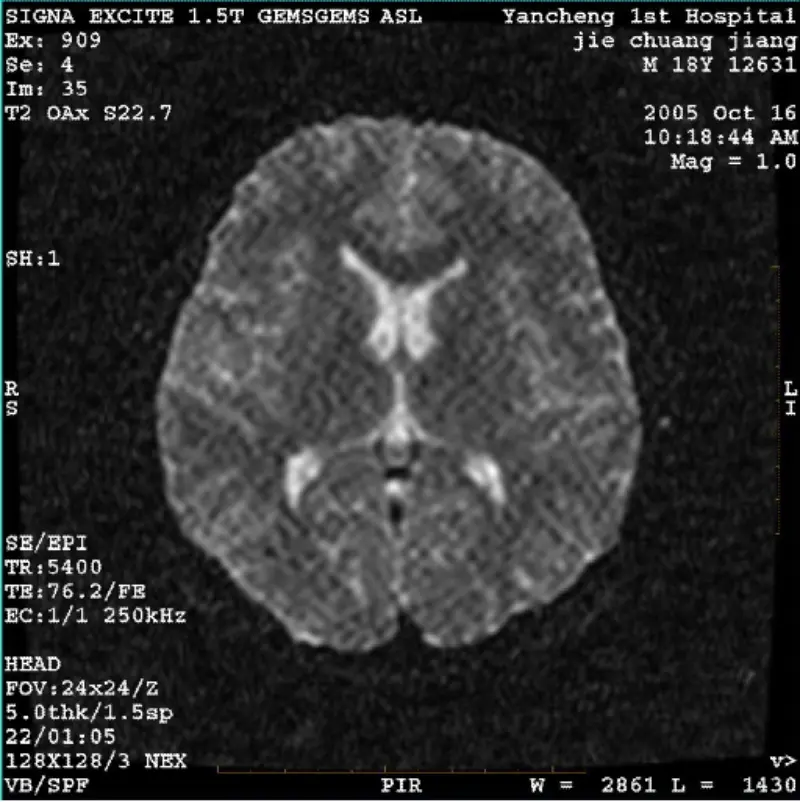

আরও পড়ুনসিস্টেম: 1.5T Signa Twin Excite II (সফ্টওয়্যার সংস্করণ 11.0M4) সমস্যা/লক্ষণ DWI (জুম মোড এবং পুরো মোড) এবং ফিয়েস্তা (জুম মোড এবং পুরো মোড) ছবি থাকা বডি কয়েল বা হেড ব্যবহার করার সময় দৃশ্যমান জালিকা বা কর্ডুরয় আর্টিফ্যাক্ট যাই হোক না কেন কুণ্ডলী, অন্যান্য রুটিন ইমেজ স্বাভাবিক মনে হয়